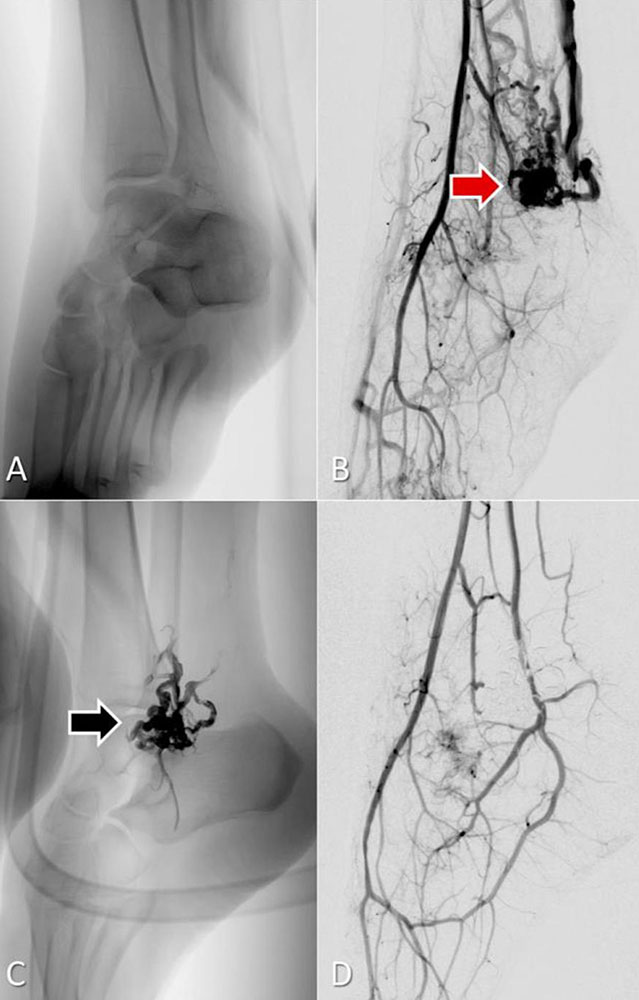

Liquid embolic agent ethylene vinyl alcohol (EVOH) copolymer

Ethylene vinyl alcohol (EVOH) copolymer is available as a mixture with dimethyl sulfoxide (DMSO) and micronized tantalum. The added tantalum ensures extremely good fluoroscopic visibility throughout the entire intervention. Upon injection through a microcatheter and contact with blood, DMSO diffuses out of the mixture, resulting in very slow, controlled precipitation of EVOH. The result is a viscous and coherent lava-like mass that can be modeled for many minutes. EVOH is mainly used in the treatment of complex arteriovenous malformations. By means of the so-called “plug-and-push” technique, the complete nidus can often be embolized from one catheter position. Since DMSO leads to irritation of the vessel wall, pain during the injection is not uncommon. It is therefore recommended that complex embolizations with EVOH be performed under general anesthesia.